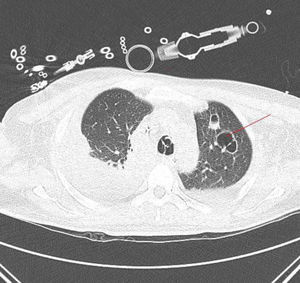

Progresivamente se observa recuperación de los fracasos orgánicos, apareciendo a nivel pulmonar múltiples nódulos cavitados en campos superiores que sugieren émbolos sépticos (fig. 2).